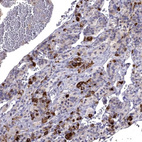

Immunohistochemistry analysis in human adrenal gland and skeletal muscle tissues using HPA074618 antibody. Corresponding SCG5 RNA-seq data are presented for the same tissues.